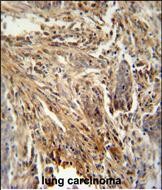

- CSF2 antibody (Center) (Cat. #P30830) immunohistochemistry analysis in formalin fixed and paraffin embedded human lung carcinoma followed by peroxidase conjugation of the secondary antibody and DAB staining. This data demonstrates the use of the CSF2 antibody (Center) for immunohistochemistry. Clinical relevance has not been evaluated.